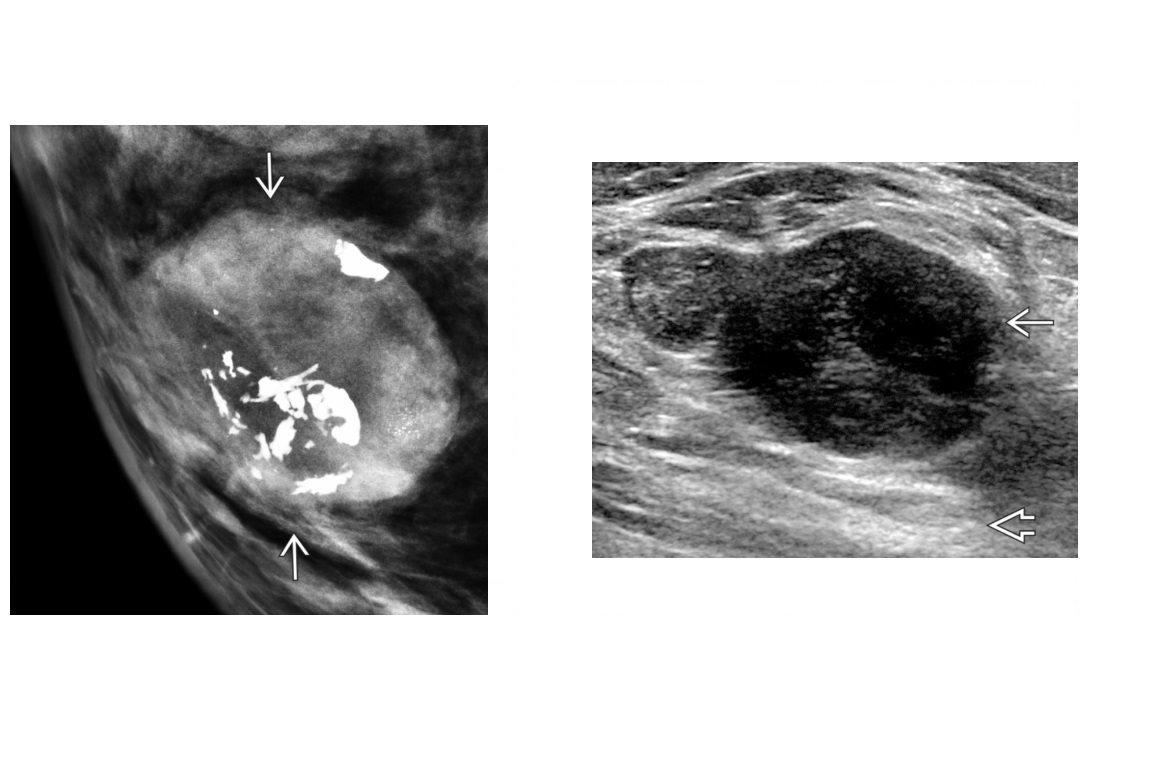

freely mobile, homogenous hypoechoic or isoechoic solid mass with

posterior acoustic enhancement (most common) and septa. thrid trimester?

A

Lactating adenoma

regresses post pregnancy

Hypoechoic, solid, circumscribed, oval or gently lobulated mass on US

May have coarse heterogeneous or popcorn Ca⁺⁺

-Galactocele:

Benign breast mass that contains retained milk

Circumscribed mass with fluid-debris level

Echogenic debris may layer in nondependent portion due to fat content of milk = Fat fluid level

Fat-containing, circumscribed mass on mammography